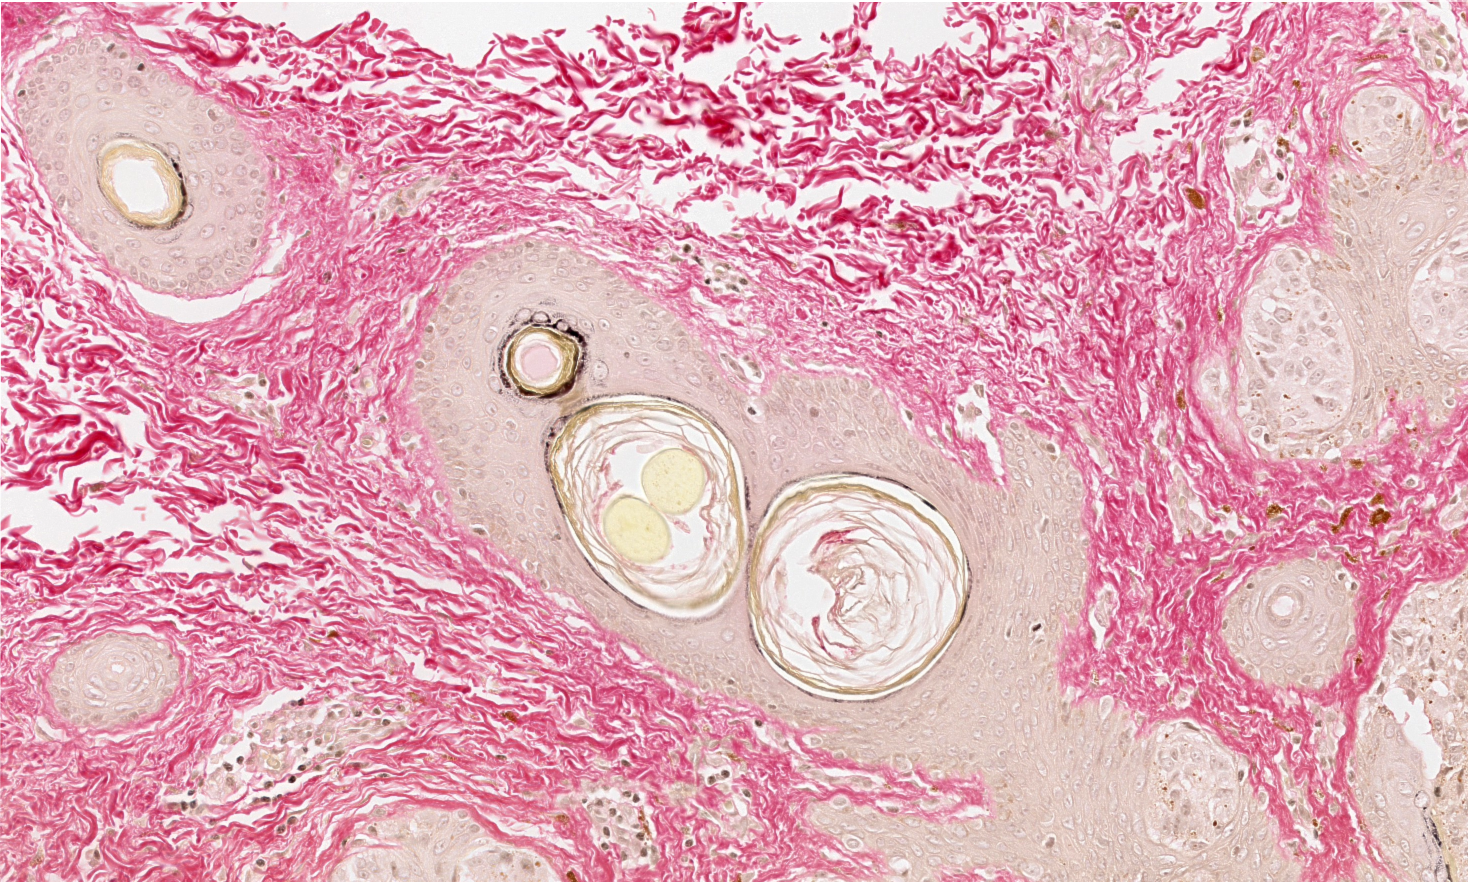

Los escáneres o digitalizadores de láminas son microscopios automatizados capaces de capturar imágenes digitales idealmente en alta resolución a partir de láminas histológicas físicas. Existen distintos modelos según el volumen y la aplicación clínica, pero para diagnóstico deben cumplir estándares estrictos de calidad y precisión.

Digitalizamos tus láminas y entregamos archivos listos para diagnóstico, revisión o docencia, con imágenes de alta resolución que cumplen estándares internacionales y que pueden ser fácilmente integradas por sistemas LIS.

Acceso a imágenes listas para revisión, discusión de casos y telepatología.

Material digitalizado para docencia, análisis y bibliotecas digitales histológicas.